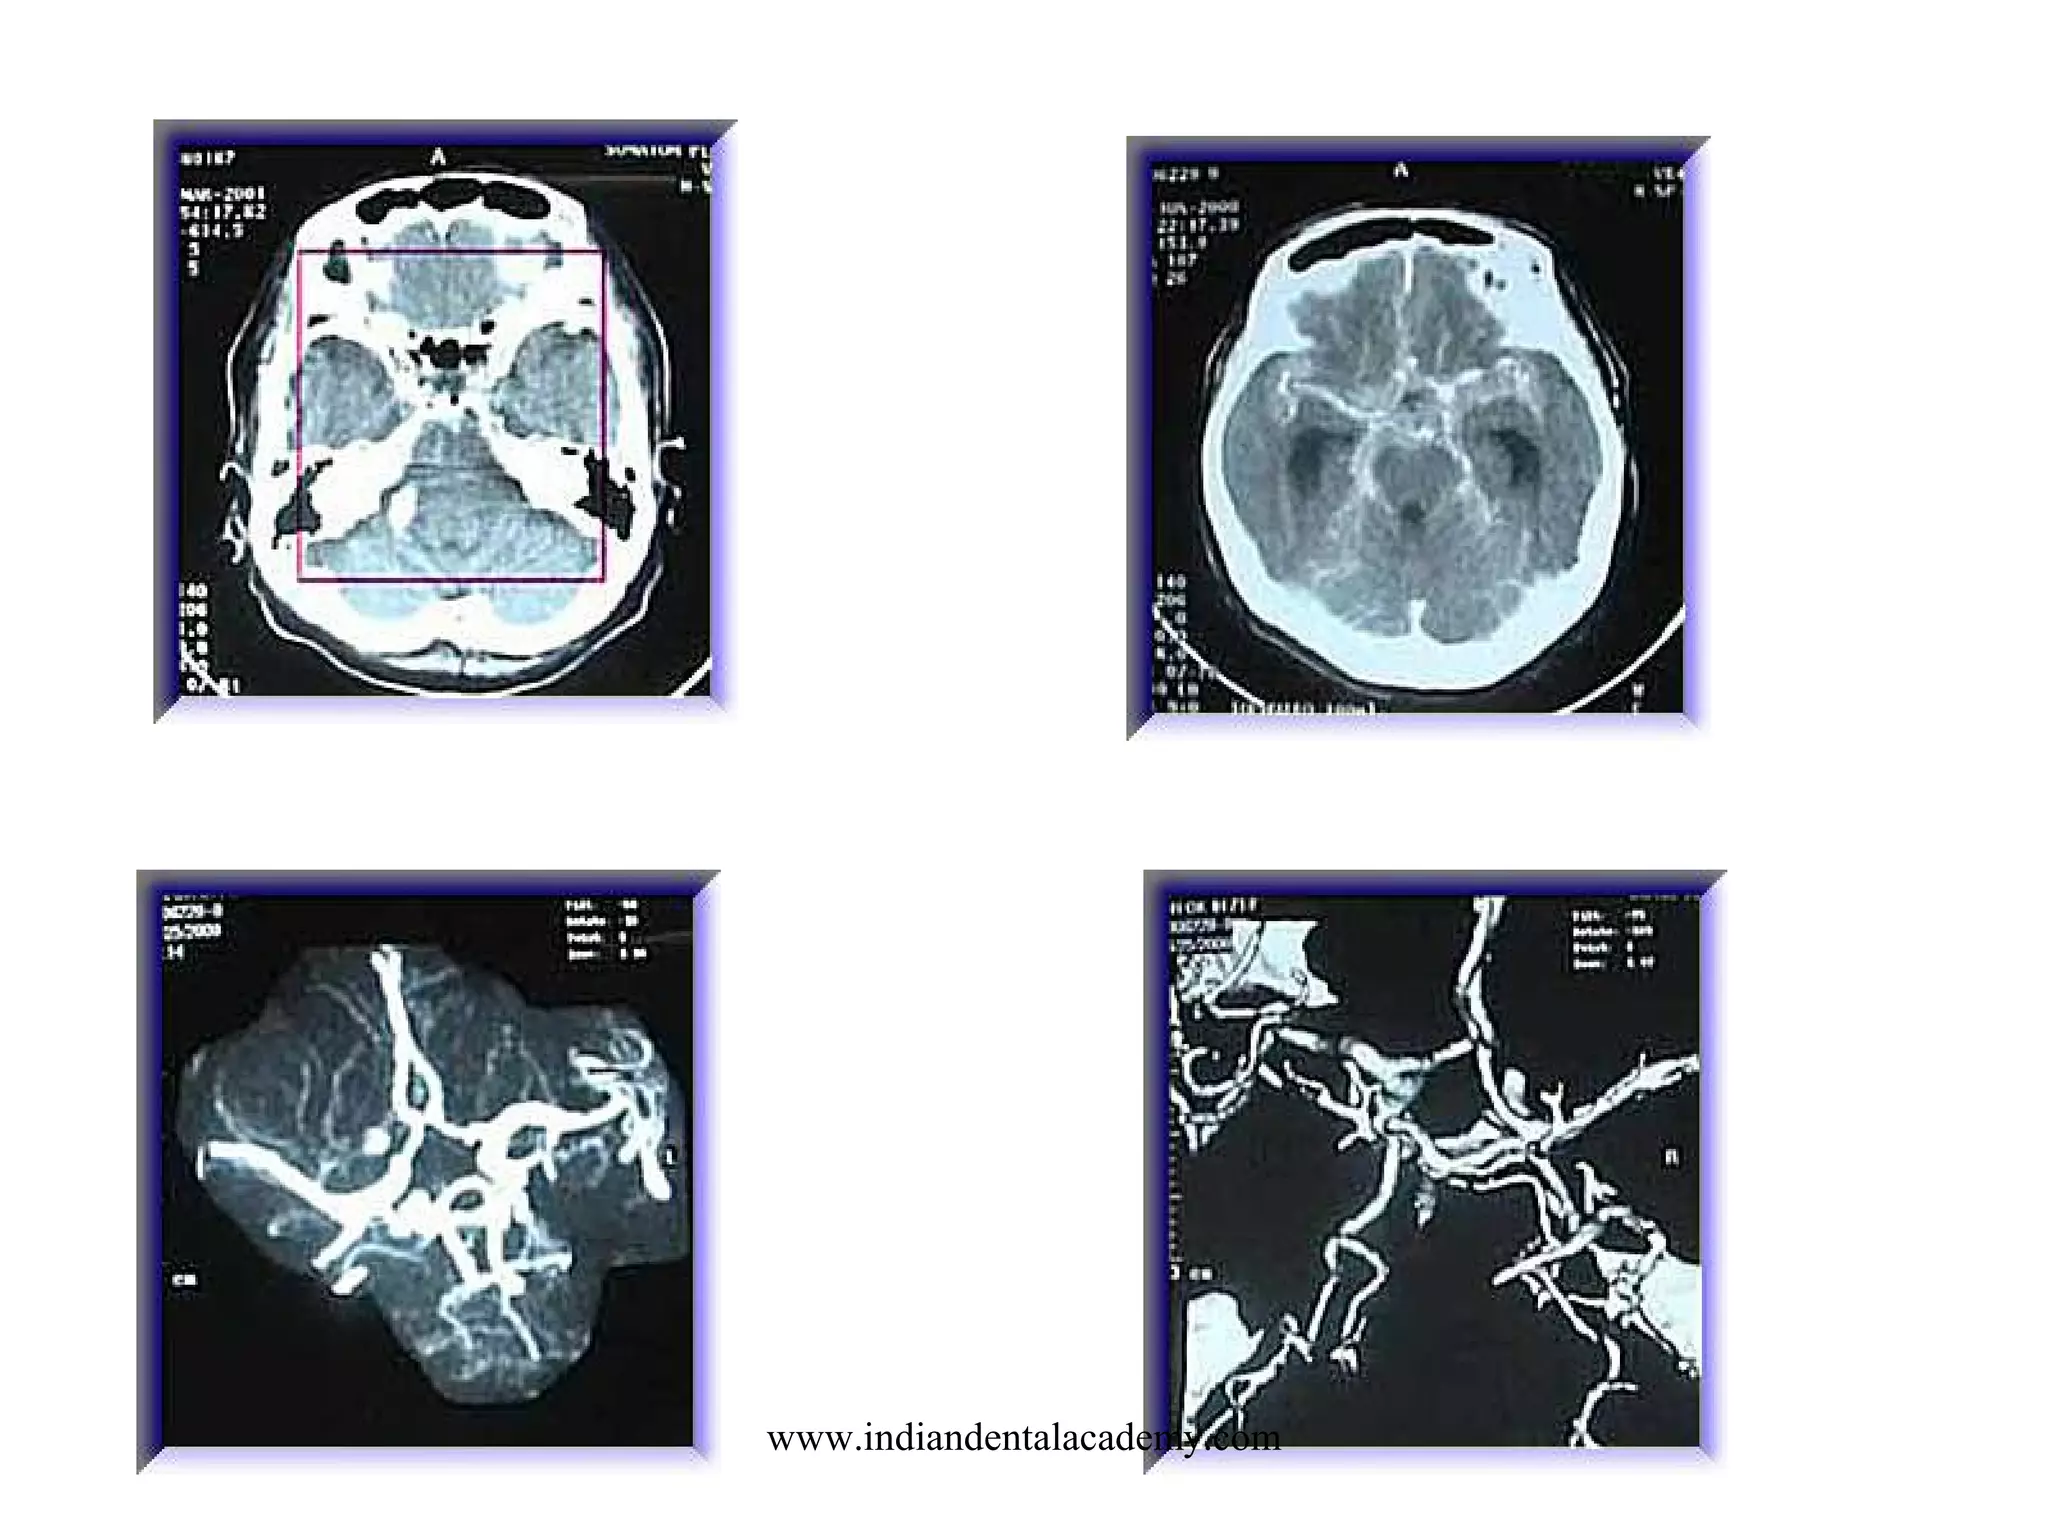

BRAIN ANGIO CTA

SCOUT: LATERAL

LANDMARK: OML

SLICE PLANE: AXIAL

I.V. CONTRAST: 100-140 ML- 3-5 ml /sec -

15 - 20 SEC DELAY CTA

30 SEC DELAY CTV

BREATH HOLD: NONE

SLICE THICKNESS: 1-2 MM

START LOCATION: BELOW SELLAR FLOOR

END LOCATION: 4-5 CM ABOVE SELLA

RECON: 50% OVERLAP

FILMING: 3 D RECON

DFOV

18

ARTERIO-VENOUS

MALFORMATION

What is a brain AVM?

Normally, arteries carry

blood containing oxygen

from the heart to the brain,

and veins carry blood with

less oxygen away from the

brain and back to the

heart. When an

arteriovenous

malformation (AVM)

occurs, a tangle of blood

vessels in the brain or on

its surface bypasses

normal brain tissue and

directly diverts blood from

the arteries to the veins

www.indiandentalacademy.com